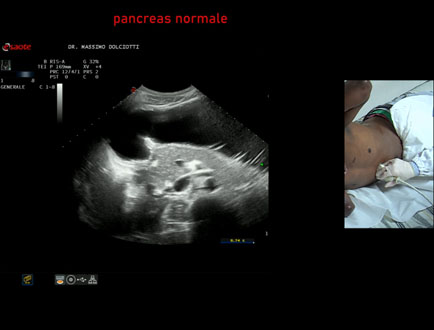

Data inserimento: 21/01/2026

Ecografia del: 14/01/2026

Strumento: Esaote MyLab Eight

Sonda: Convex Multifrequenza 1-8 MHz

Età Paziente: M 29 anni

Motivazione dell'esame: epatopatia virale

Commento all'esame: le immagini ed il video documentano il pancreas ipoecogena, di ecostruttura e morfovolumetria regolare, esaminato in posizione supino e laterale destra.

Conclusioni: pancreas normale (normal pancreas).

In collaborazione: Dr.ssa Marica Manfredi - Ancona, Dr. Ilir Qose - Ancona

Presentazione: Dr. Massimo Dolciotti - Ancona